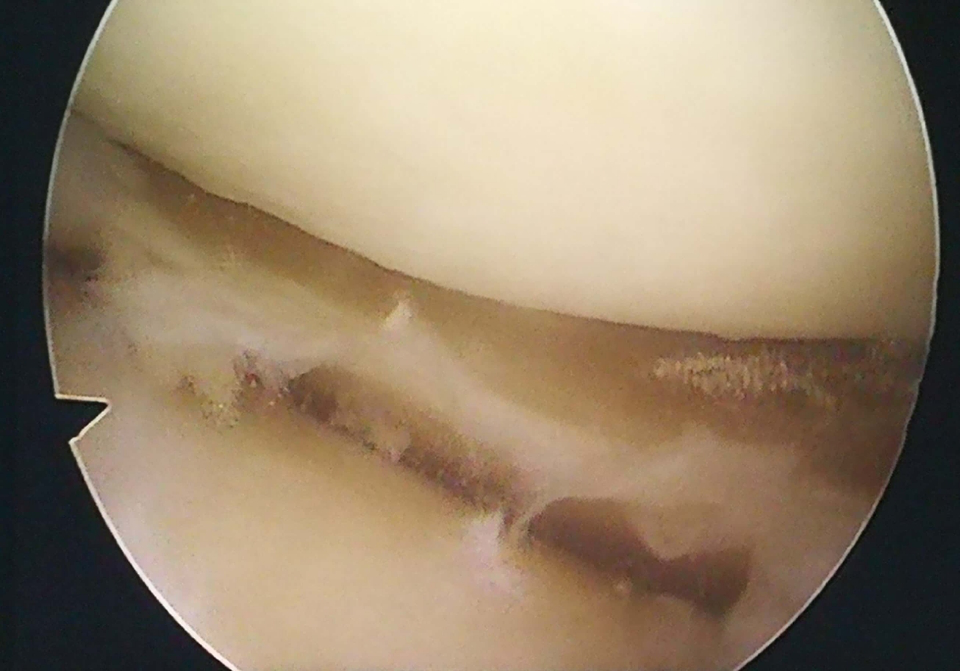

术中关节镜下显示:患者左膝内侧间室软骨剥脱,软骨下骨裸露,外侧间室关节软骨正常,半月板损伤